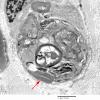

PERIPHERAL NEUROPATHY

4 AXONAL DEGENERATION

3 Electron Microscopy (2)